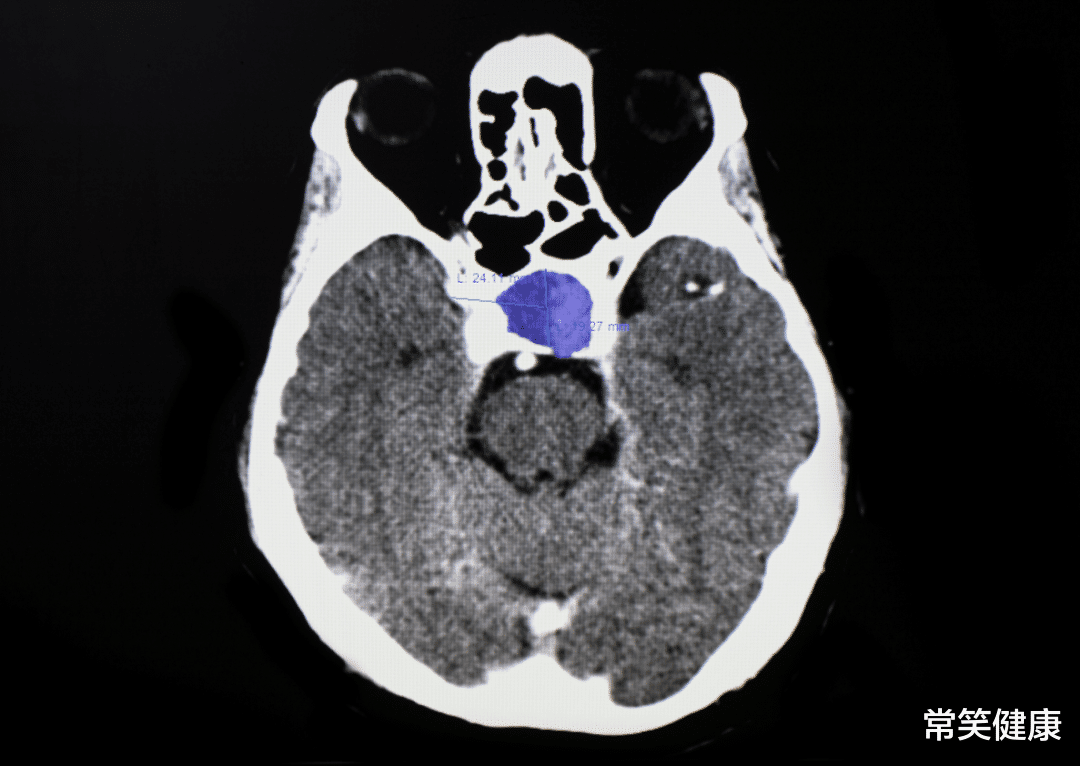

至于垂体为什么会病变 , 至今还是有争议的 , 可能与基因突变、家族遗传、下丘脑调控激素紊乱有关 。 不过这类疾病发生的年龄段还是蛮广泛的 , 30-60岁 , 发病率也在脑肿瘤中位列前排 , 不过好在多为良性 , 通过手术拿掉后 , 基本问题不大!所以 , 得了垂体瘤也没必要太过焦虑 , 垂体瘤也不是什么疑难杂症 , 一般的垂体腺功能、甲状腺功能、肾上腺动能、性腺功能等检查都可以及时诊断出来 。 如果还是不放心 , CT、核磁共振也可以及时发现垂体瘤的存在 。